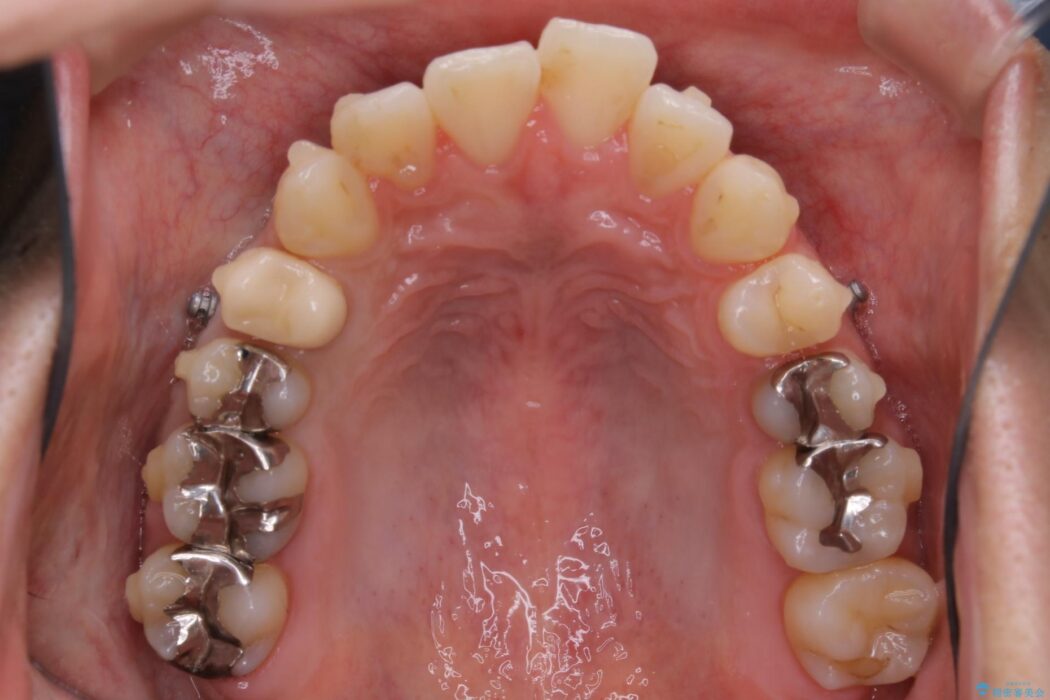

歯列のガタガタと飛び出ている前歯を治したいとのことで来院されました。

装置の範囲内で可能な限り前歯の位置を動かし整えるため、マイクロインプラントを用いて遠心移動をする歯列矯正を計画しました。

マイクロインプラントについて

本症例では上顎前突(出っ歯)や歯列のがたつきを改善するスペースを確保するために、歯を遠心移動をサポートすることができるマイクロインプラントを用いたゴムかけを行っていただきました。